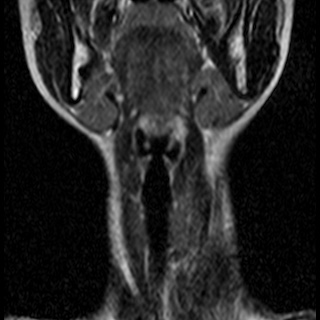

Невринома множественная шейного отдела с врастанием в спинно-мозговой канал

Здравствуйте! Мне 27 лет. Я стала жаловаться на головокружение, головные боли, пульсирование в голове. После исследования мрт выявилась следующая патология . Документы предоставляю. Можете ли Вы помочь в этой патологии? Как попасть к Вам на консультацию, учитывая эпидемиологическую обстановку? Спасибо.